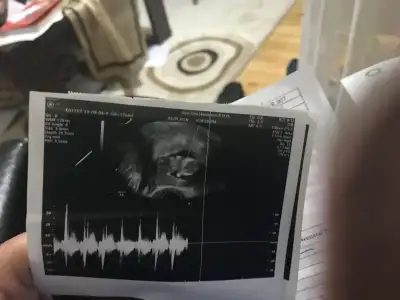

dr soylemeden siz gorun genital nub teorisi ( bebegin cinsiyeti)

Usg net degil ama Erkek gibi sankiİyi akşamlar kızlar. 11+6 haftaligiz. Bizde yorum alabir miyiz :)

Başka usg varmı nub göremedim kafa yapısı erkek gibi tutmayada bilirİyi akşamlar kızlar. 11+6 haftaligiz. Bizde yorum alabir miyiz :)

Merhaba arkadaşlar.Bize de yorum yapabilirseniz çok seviniriz 11+6 günlük

11+6 günlük

Kafa yapısına göre erkek ama tutmaya bilir nub görünmüyor 11 yada 12 hafta varsa tahmin ederimMerhaba hanımlar

bugün doktora gittim fakat ogrenemedım secde pozisyonunda durdu hep bebegım

Tahmınınız varsa yapın lutfen 13 haftalık

Erkek tam net degil usg başka varmı netleştirim tahminim şimdilik erkek diyorum ve kaç haftalıkMerhaba bu ultrason görüntüsü bir akrabamin yorumunuzu bekliyorum :)